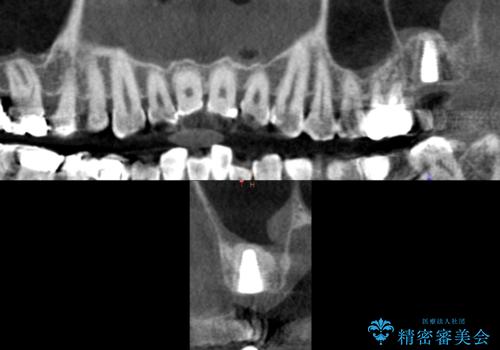

奥歯でしっかりと咬むことができるようになり、ご満足頂けました。

初診時から治療終了時までのレントゲンをお見せして説明差し上げたところ、「お~!骨ができている!」と喜んで下さいました。

ソケットリフトにより上顎洞底を挙上し骨造成することにより、骨の厚みが薄い部分でもインプラントが可能になります。

インプラントの種類:ストローマン BLT

クラウンの種類:メタルボンドクラウン エコノミー